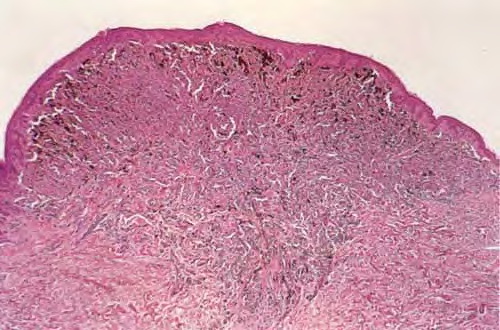

Deep plantar wart = ثؤلول أخمصي عميق